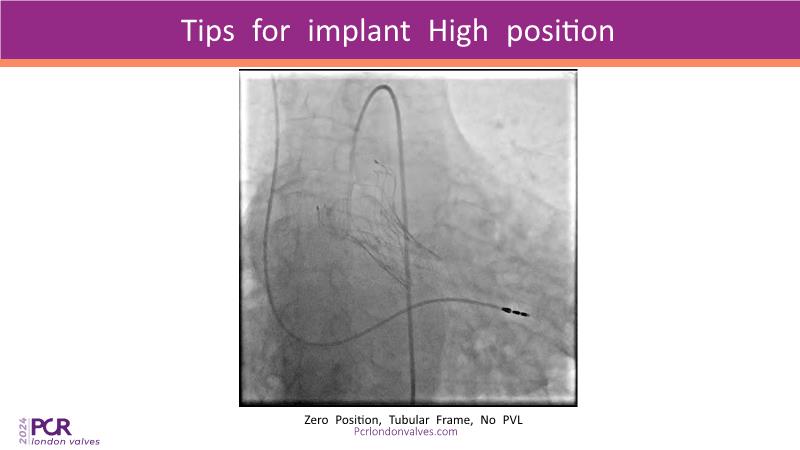

- To discuss the procedural steps needed to treat bicuspid aortic stenosis with self-expanding devices

- To review a step-by-step implant of the VitaFlow TAVI system in bicuspid aortic stenosis